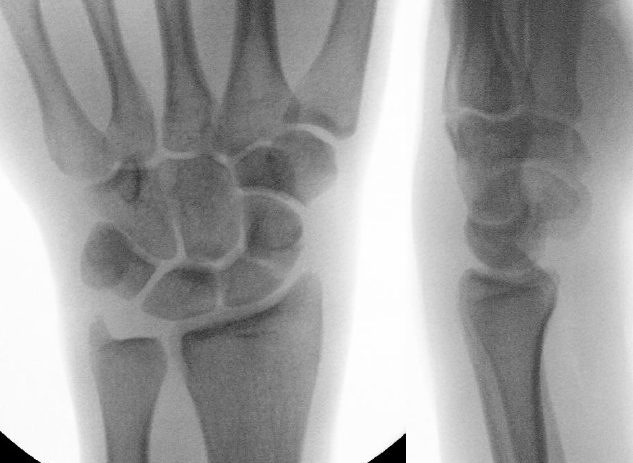

AP X-ray

Disruption of Gilula's 3 smooth carpal arcs / triangular lunate

Normal versus disruputed Gilula's carpal arcs

Piece of pie / triangular appearance of lunate

Lateral xray

Distal radius / lunate / capitate: not aligned, spilled teacup

Normal versus spilled tea cup appearance on lateral with spilled tea cup

CT

Trans-scaphoid perilunate dislocation

Perilunate dislocation